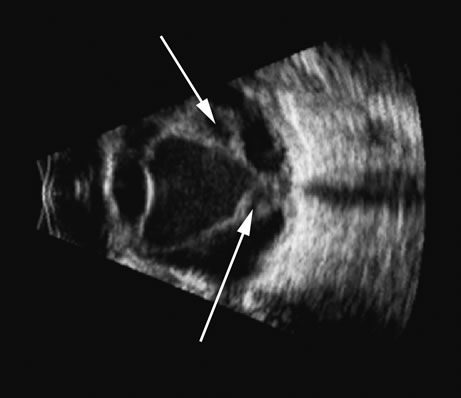

The retina is a highly reflective surface (specular reflector) and can be seen to always maintain its connection to the optic nerve, even when drawn into an organized detachment. It may not be attached at the ora serrata in giant tears, but otherwise it generally maintains the two “landmark” attachments of optic nerve and ora serrata (Fig. 13), which can aid in differentiating the retina from the PLM of the retracted vitreous and from the choroid, in which the detachment may extend anterior to the ora and rarely extend back behind the vortex veins to the nerve (Fig. 14).14

Fig. 14. A B-scan of an eye with “kissing” choroidal detachments. The smooth convex outline from the ciliary body back to the near periphery of the posterior pole can be seen. The choroidal space, though filled with blood, may often appear anechoic due to the recent, “fresh” nature of the hemorrhage.